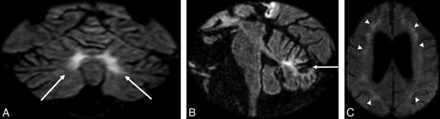

Representative case (patient 1). A 49-year-old male patient with a genetically confirmed diagnosis of FXTAS (CGG 115). Coronal (A) and sagittal (B) FLAIR images demonstrate cerebellar atrophy and a high signal intensity in the paravermal area (arrows). C, DWI shows abnormal high-intensity signal along the corticomedullary junction (arrowheads).

Representative case (patient 2). A 69-year-old male patient with slowly progressive ataxia, tremor, and paraparesis. Axial FLAIR image (A) shows bilateral abnormal high signal intensity in the middle cerebellar peduncles (arrows). Axial DWI (b = 1000 s/mm2) (B) image depicts similar signal changes along the corticomedullary junction (arrowheads). Genetic investigation showed 100 CGG repetition (premutation) of the FMR1 gene, which confirmed FXTAS.